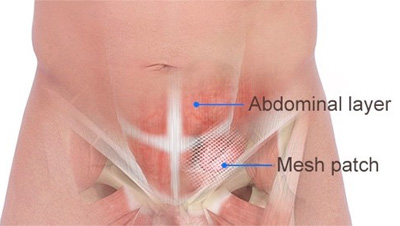

Overview

Package includes:

Days in hospital : 3 to 4 Days (For patient and one attendant)

Days in hotel : 15 Days (For patient and one attendant)

Room type in hospital : Shared

Room type in hotel : Private

Hotel category: Standard

Value added benefits of the Hernioplasty Inguinal with Mesh:

Ø Doctor consultation charges

Ø Lab tests and diagnostic charges

Ø Room charges inside hospital during the procedure

Ø Surgeon Fee

Ø Nursing charges

Ø Hospital surgery suite charges

Ø Anesthesia charges

Ø Routine medicines and routine consumables (bandages, dressings etc.)

Ø Food and Beverages inside hospital stay for patient and one attendant.

Extra benefits:

ü Interpreter

ü Visa assistance

Ø Site tourism of the city

Ø Follow up with the doctor

Ø Airport pick up and drop

Ø Free online consultation with the doctor

Ø Priority appointments with the doctor

Ø Room upgrade from sharing to private

Overview

Package includes:

Days in hospital : 2 to 3 Days (For patient and one attendant)

Days in hotel : 15 Days (For patient and one attendant)

Room type in hospital : Shared

Room type in hotel : Private

Hotel category: Standard

Value added benefits of the Hernioplasty Inguinal Bilateral with mesh:

Ø Doctor consultation charges

Ø Lab tests and diagnostic charges

Ø Room charges inside hospital during the procedure

Ø Surgeon Fee

Ø Nursing charges

Ø Hospital surgery suite charges

Ø Anesthesia charges

Ø Routine medicines and routine consumables (bandages, dressings etc.)

Ø Food and Beverages inside hospital stay for patient and one attendant.

Extra benefits:

ü Interpreter

ü Visa assistance

Ø Site tourism of the city

Ø Follow up with the doctor

Ø Airport pick up and drop

Ø Free online consultation with the doctor

Ø Priority appointments with the doctor

Ø Room upgrade from sharing to private